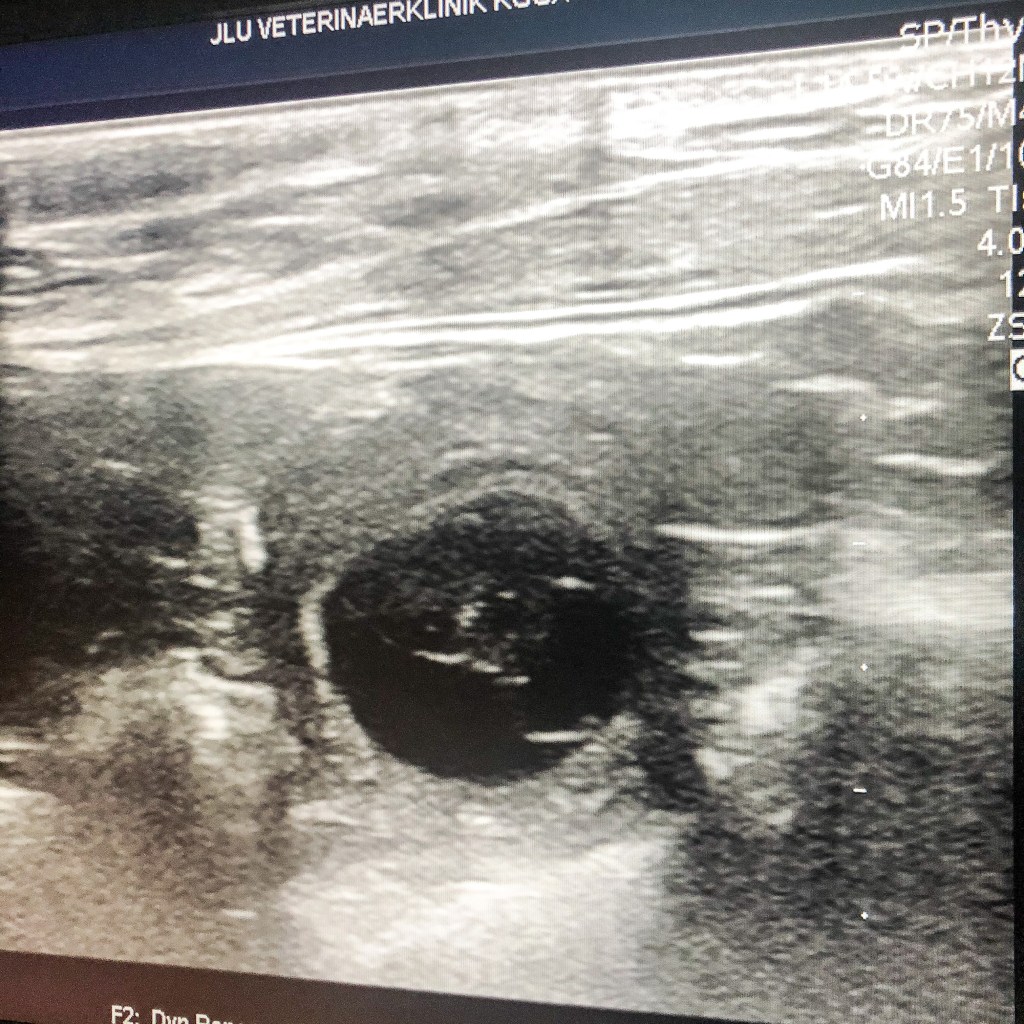

Am 12.10.2020 hat die Ultraschalluntersuchung in der Uniklinik für Veterinärmedizin Gießen ergeben, dass Käthe tragen ist. Wir erwarten um den 19. November einen normal großen Wurf.